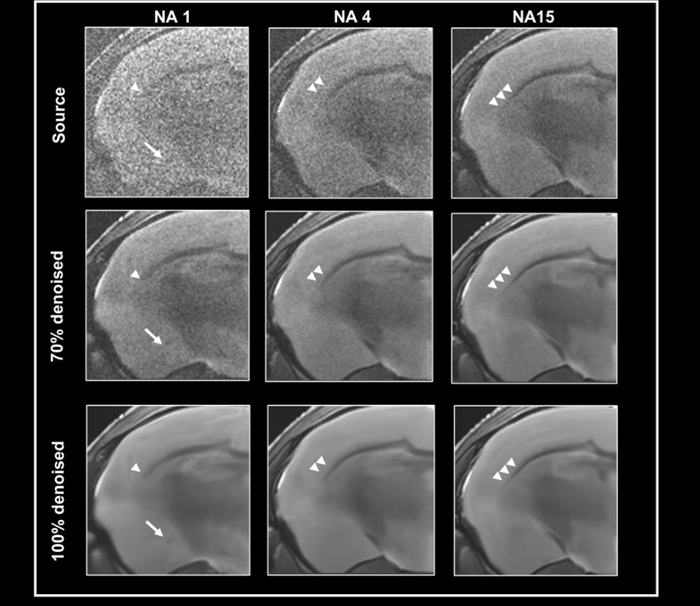

To test the efficacy of the denoising algorithm with images of varying levels of tissue contrast, ex vivo data of a fixed mouse brain was obtained with a nominal voxel size of 55 x 55 x 800 µm3 at 3 Tesla, either with no averaging, 4, or 15 averages (Fig 3).

The contrast-to-noise ratio for the corpus callosum and cortex is 2.47±0.45, 4.59±0.01, and 12.03±0.81, respectively. Images were reconstructed without 70% and 100% denoising.

Given the relatively high resolution, the image without averaging has low tissue contrast and noise, which can be reduced by utilizing averaging during acquisition or denoising during reconstruction.

Comparing denoised images taken with varying average numbers demonstrates that denoising might magnify false contrast in circumstances of low tissue contrast, i.e. no averaging (Fig 3, arrow).

Figure 3. Denoising images with low tissue contrast. A) Axial T2-weighted TurboRARE images of a fixed mouse head were acquired at 3 Tesla with 1, 4 and 15 number of averages (NA), respectively. Images have a nominal voxel resolution of 55 x 55 x 800 μm3. Image reconstruction was performed without (Source) and with 70 % and 100 % denoising. Each denoised image was reconstructed with a network Strong and a pre-denoising of 50 % was applied. The arrows point to a structure in the NA1 images, that is faintly visible in the image that has not been denoised and that becomes more apparent with increasing denoising. The arrowheads point to the corpus callosum which becomes more visible. Resolution of fine structure requires high tissue contrast with averaging. Image Credit: Bruker BioSpin Group

This structure, which is slightly visible in the noisy image without denoising but is difficult to differentiate from the surrounding tissue, is improved by raising the level of denoising.

A comparison of images with varying amounts of averaging shows that denoising makes the corpus callosum more visible. To resolve the fine structure of the corpus callosum's extent, strong tissue contrast and averaging are required. If this is the case, denoising improves visualization.